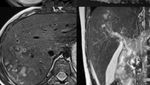

Jakarta - Beberapa hewan kurban dilaporkan terjangkit oleh cacing hati. Parasit ini bisa menyerang hewan dan juga manusia menyebabkan penyakit fascioliasis.

Foto: Melihat Lebih Dekat Cacing Hati yang Menginfeksi Hewan Kurban